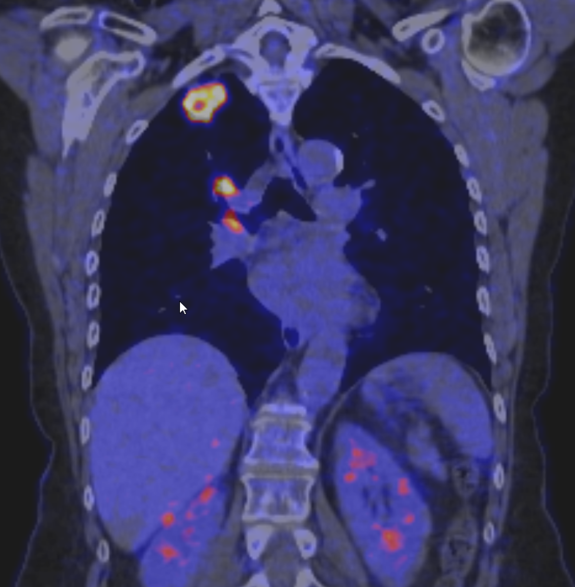

In der interdisziplinären Tumorkonferenz der Fachkliniken Wangen stehen die Patientinnen und Patienten im Mittelpunkt. Expertinnen und Experten aus verschiedenen Fachrichtungen – darunter Thoraxchirurgie, Pneumologie, Onkologie, Radiologie, Pathologie, Strahlentherapie, Nuklearmedizin und Palliativmedizin – besprechen gemeinsam die vorliegenden Befunde und entwickeln auf dieser Basis eine individuelle Therapieempfehlung.

Das Tumorboard ist dabei ein wichtiger Bestandteil der diagnostischen Kette. Es verknüpft die Ergebnisse aus Bildgebung, Labor, Endoskopie und Pathologie zu einer fundierten Gesamteinschätzung. So entsteht eine sichere Grundlage für alle weiteren Therapieentscheidungen.